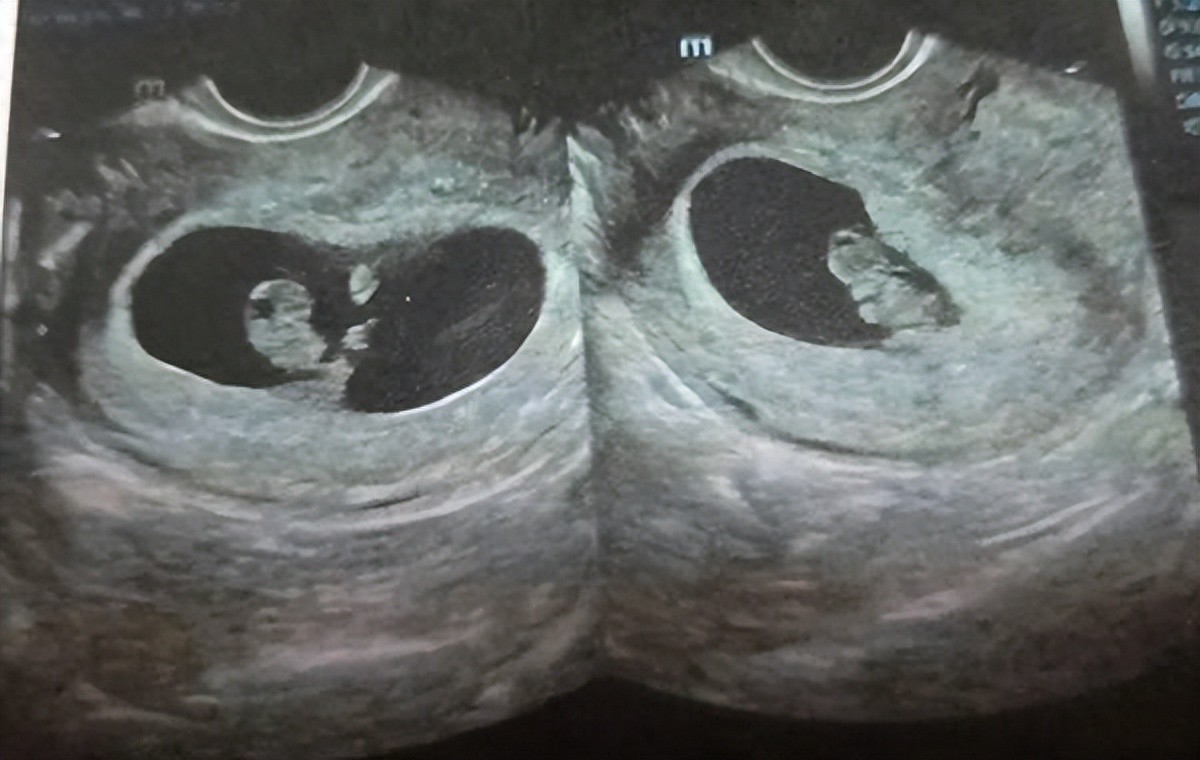

搜索引擎里关于“孕囊看男女”关键词比比皆是,各种经验分享、图片对比,甚至还有人信誓旦旦地宣称“准确率高达99%”,准妈妈们热烈地讨论着B超单上数据,试图从那些数字和形状中,找到关于宝宝性别蛛丝马迹,孕囊像茄子,十有八九是男孩;也有人说,孕囊长宽比例相差大,怀肯定是小王子,究竟是民间智慧结晶,还是缺乏科学依据臆测?

要解开这个谜题,我们需要先解一下孕囊,孕囊就像一个温暖“小房子”,胎宝宝就里面安心地住着,它最早出现B超上,通常是怀孕6周左右,是孕早期检查重要指标之一,医生会通过观察孕囊大小、形状、位置等,来判断胎儿发育情况

孕囊形状和大小,真和胎儿性别有关吗?民间流传说法五花八门,有看似有理有据,有则显得有些荒诞,男孩发育速度快,孕囊会更长一些;也有人说,女孩性格文静,孕囊会更圆润一些,听起来似乎有些道理,但实际上缺乏科学依据

孕囊形状和大小,主要受到以下几个因素影响:孕妇自身条件,比如子宫大小、形状等;怀孕周数,孕囊自然也会越大;以及胎儿发育情况,比如胎儿发育速度、姿势等,而胎儿性别,是由染色体决定,并不会直接影响孕囊形态